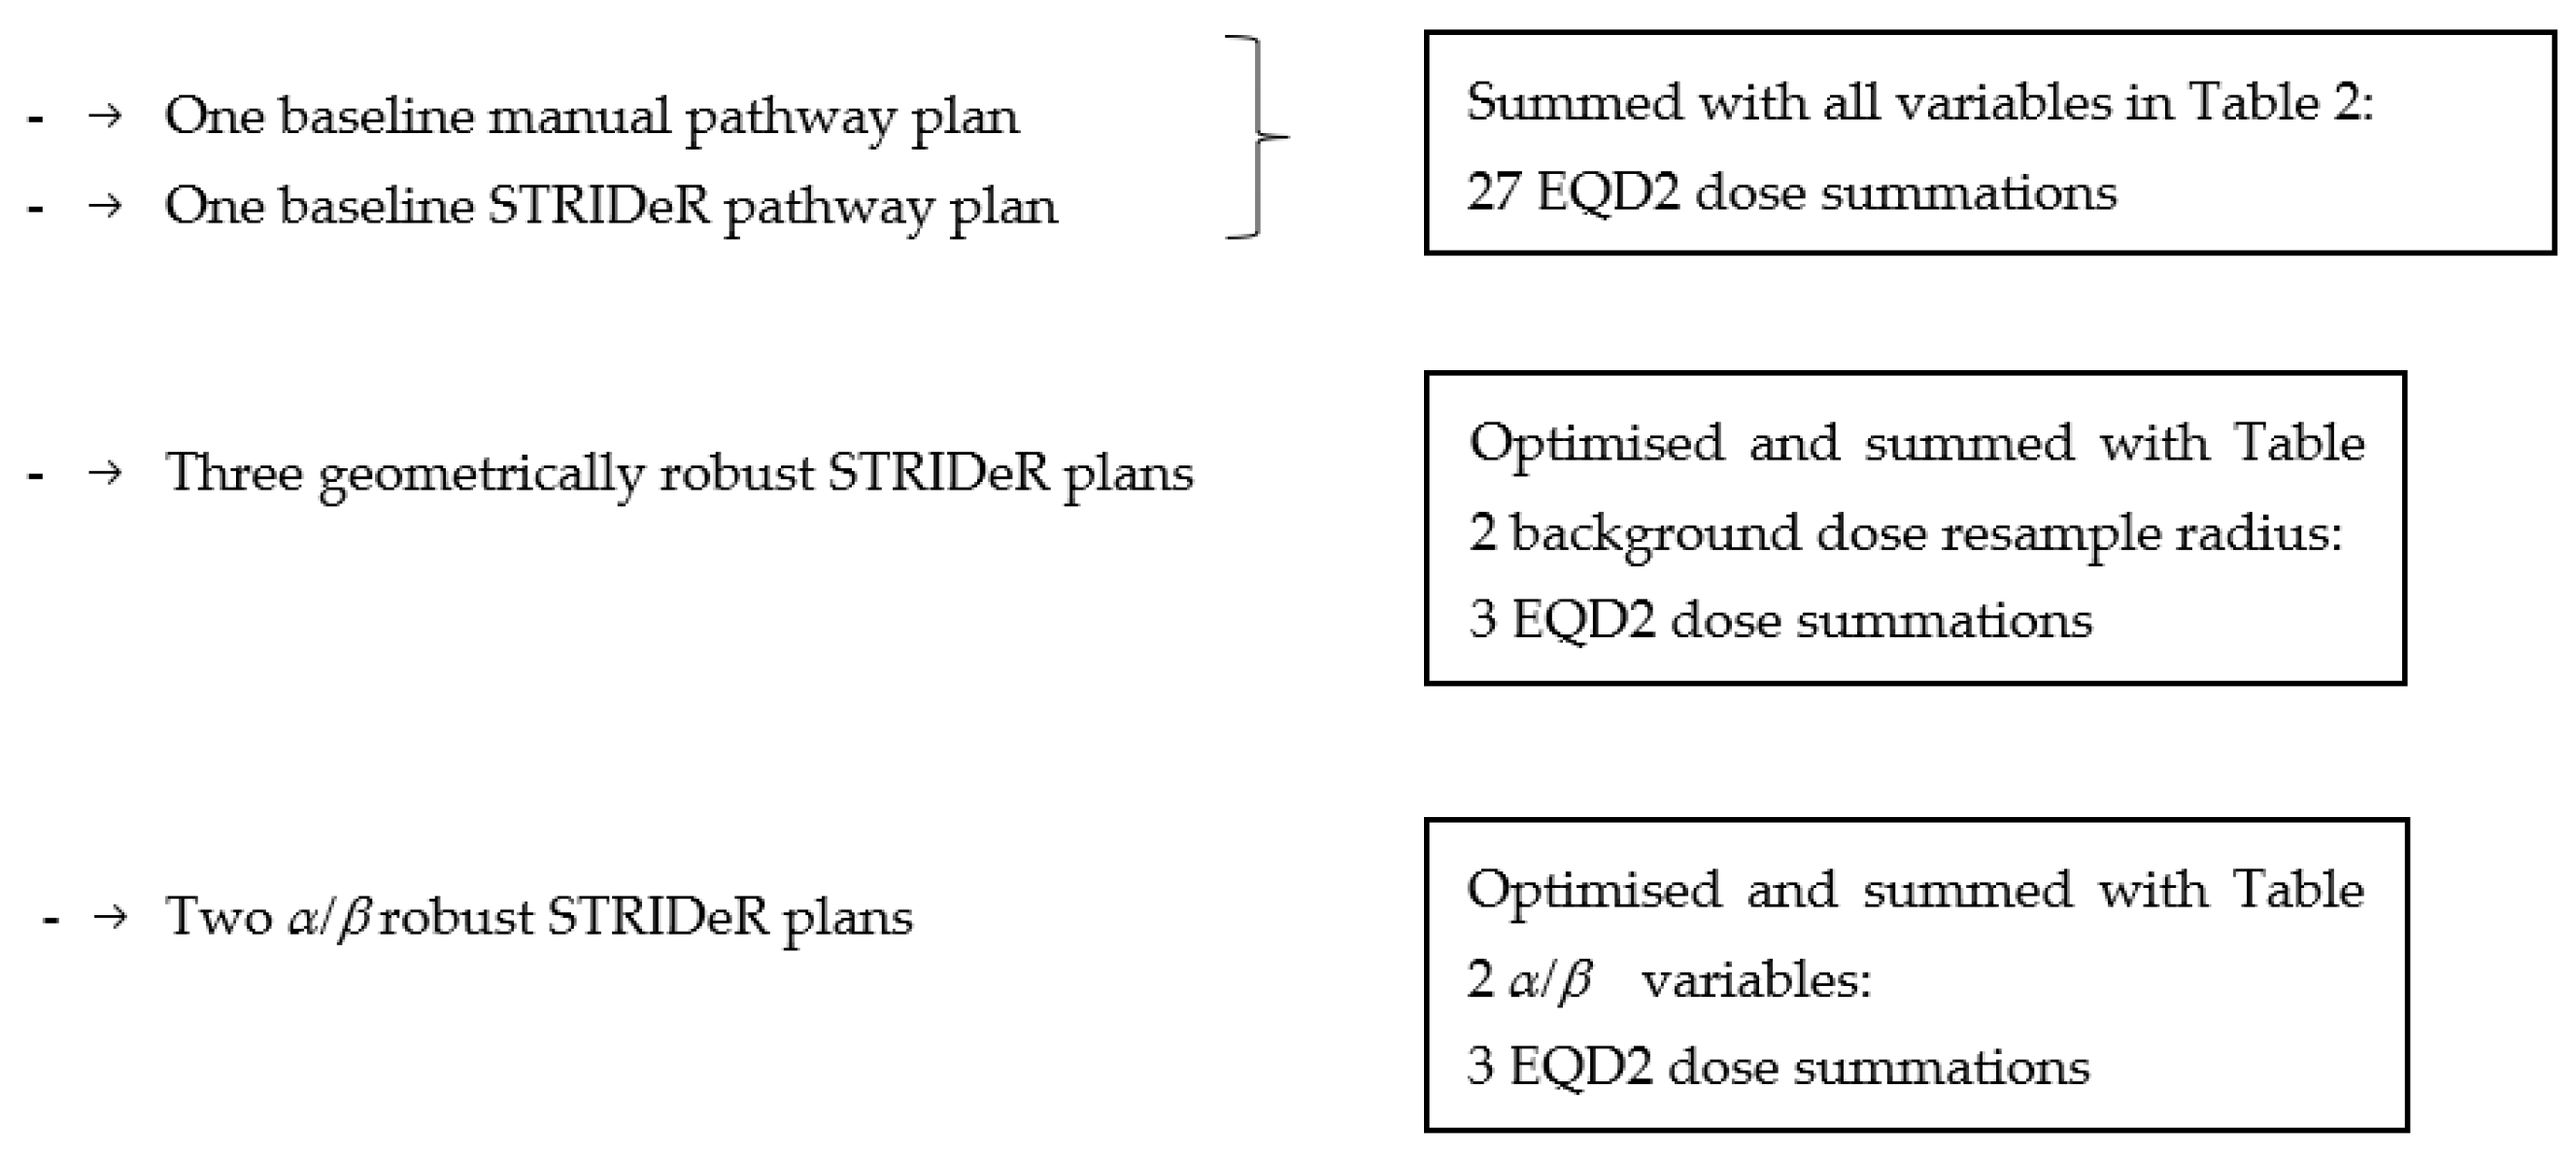

2.6. Robustness Evaluation (Re-Summed Plans)

2.7. Robust Optimisation

3.2.1. Geometric Robustness

3.2.2. Fractionation Sensitivity

3.2.3. LQ Model Robustness